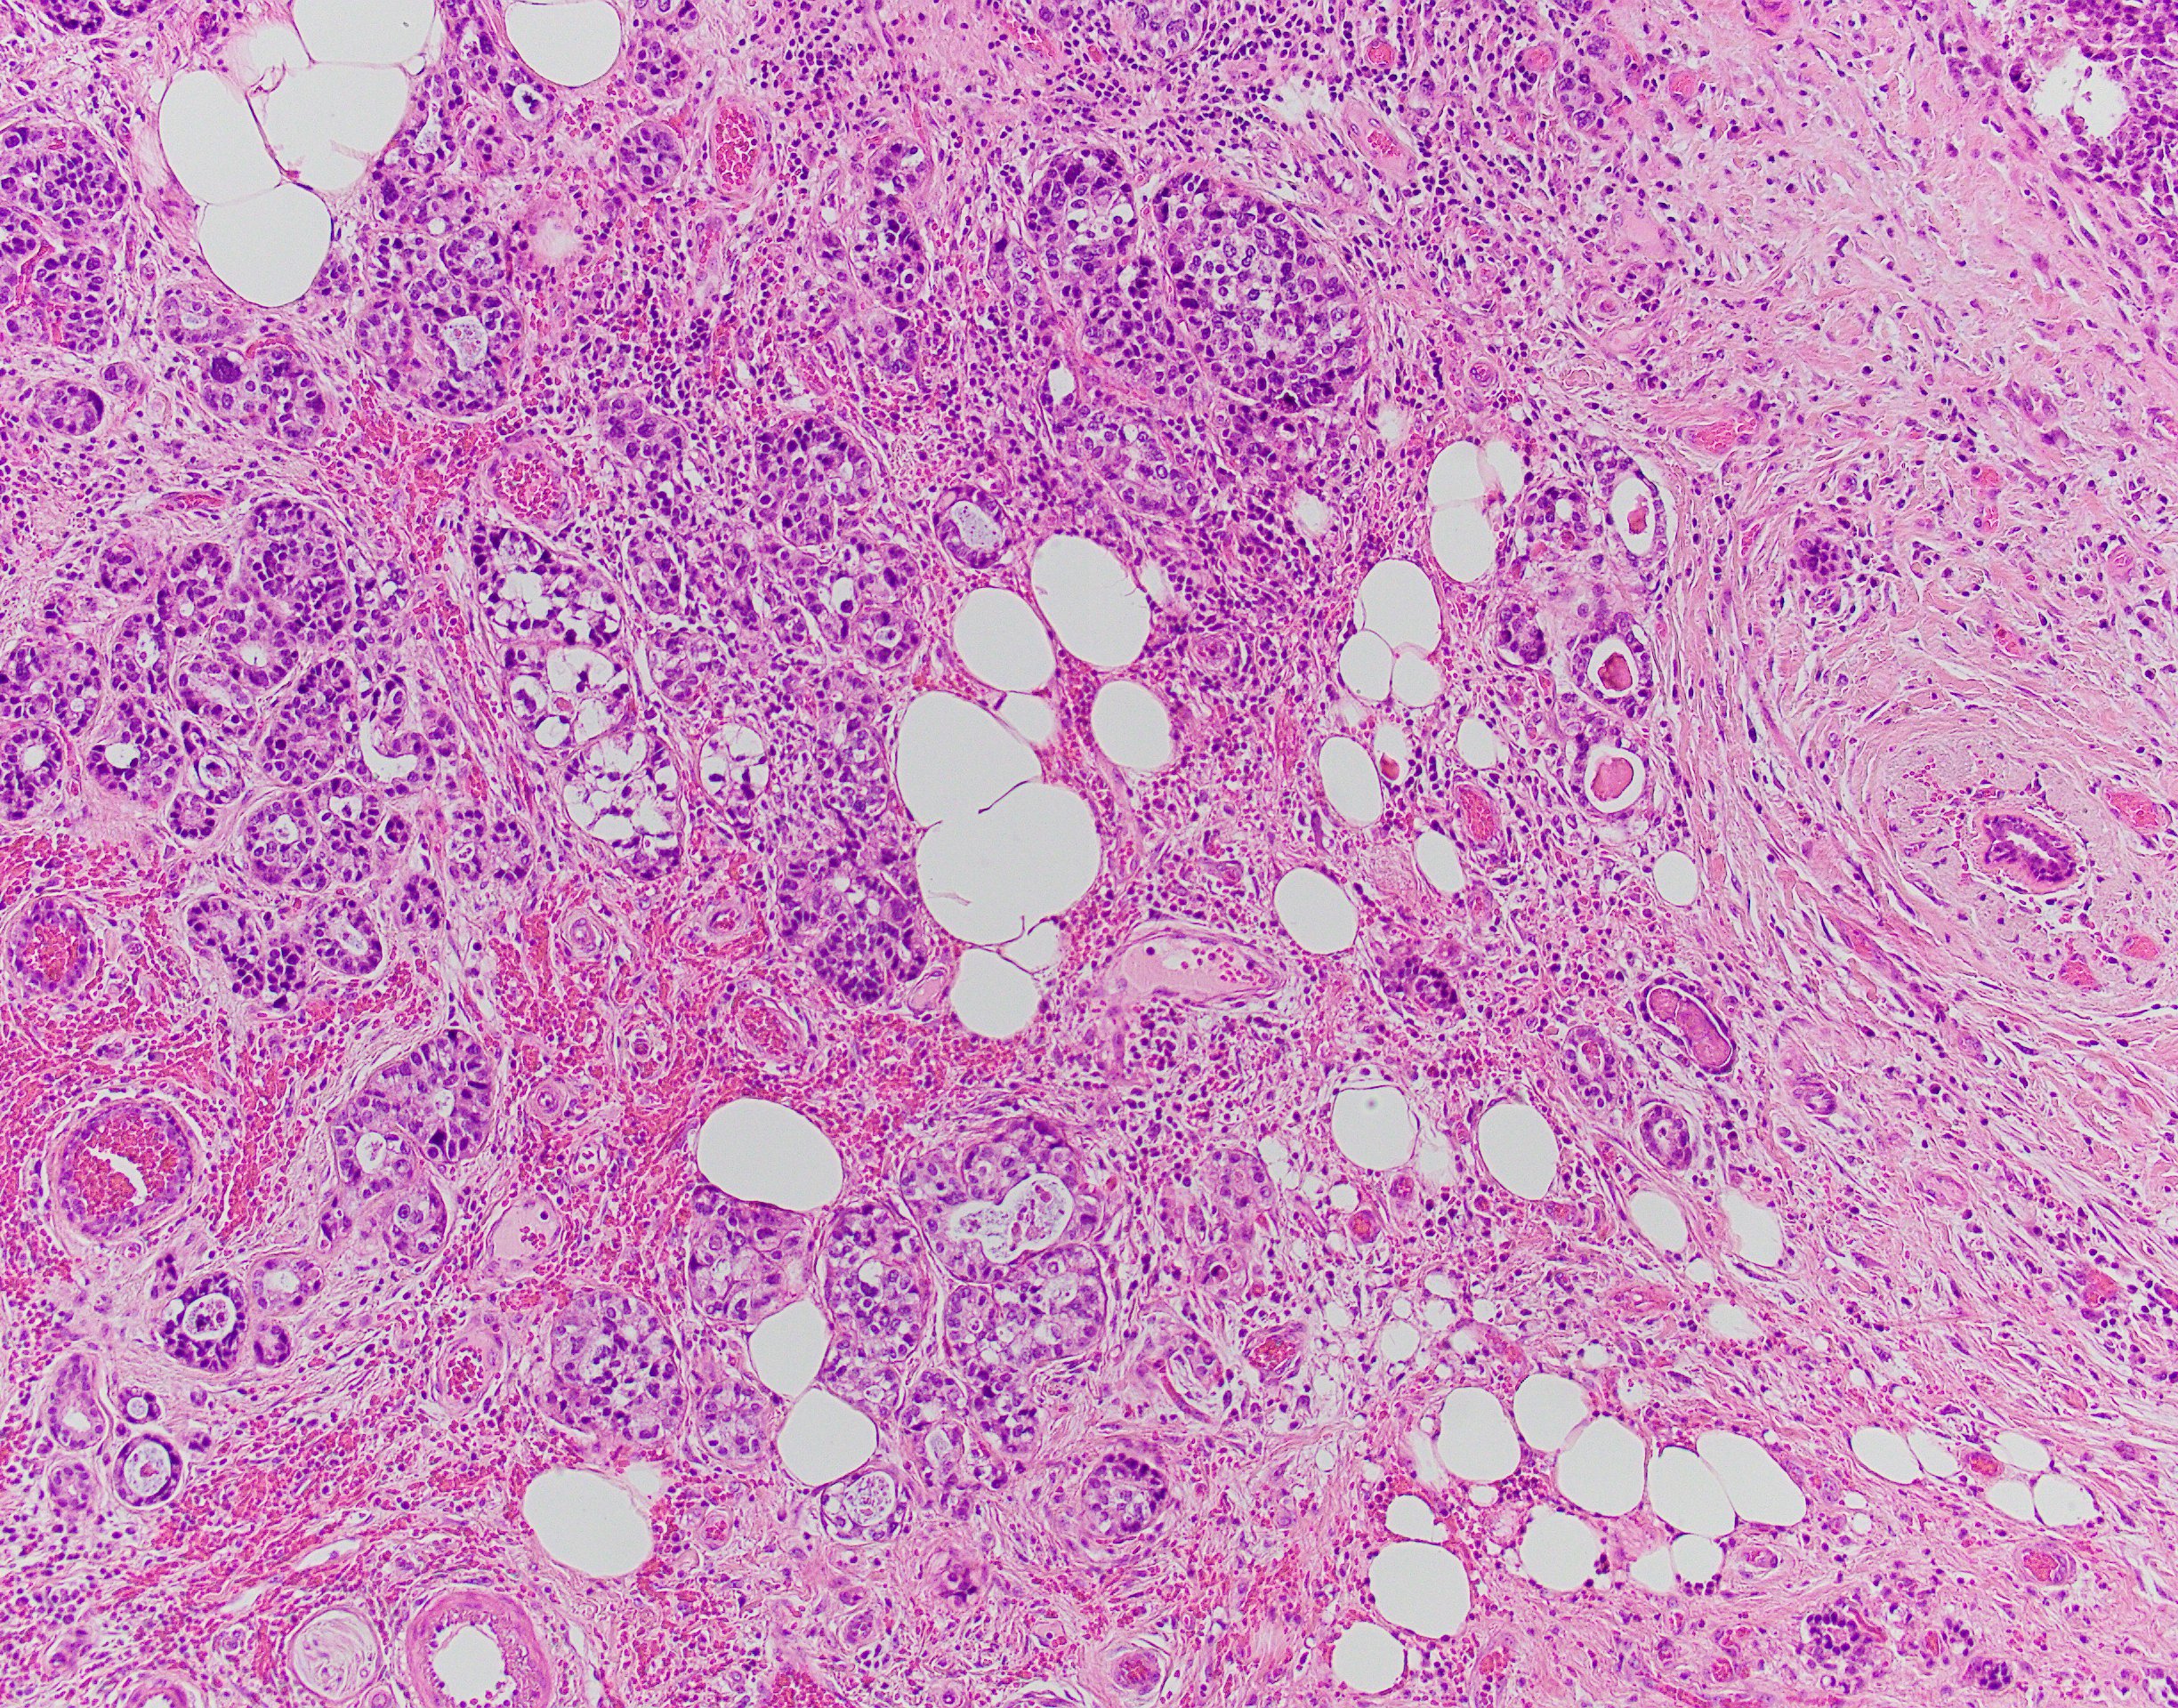

Acinic cell carcinoma (ACC) is a rare histological type of malignant epithelial neoplasms characterized by widespread acinar cell-like differentiation.

The ACC of the breast was first described in 1996 by Roncaroli et al. The histological pattern of these cases is predominantly solid with a microglandular structure, with associated cystic or/and papillary components.

ACC is characterized by serous acinar differentiation with zymogen-type cytoplasmic granules. The immunohistochemical profile of breast Acinic cell carcinoma shares many features with Acinic cell carcinoma of the salivary glands, with frequent expression of GCDFP-15, S-100, and a-1-Antichymotrypsin, as well as PAS-D positivity.

The differential diagnosis are microglandular adenosis and granular cell carcinomas (apocrine carcinomas, secretory carcinoma, oncocytomas and neuroendocrine carcinomas)